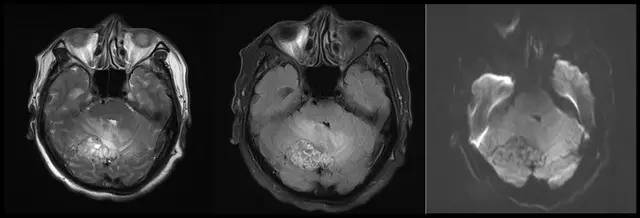

图 2 右侧小脑半球见不规则异常信号,T1WI呈低信号,T2WI及FLAIR呈稍高信号,病灶周围见紊乱迂曲血管影,增强扫描呈明显强化;四脑室受压移位、变窄,幕上脑室系统扩张